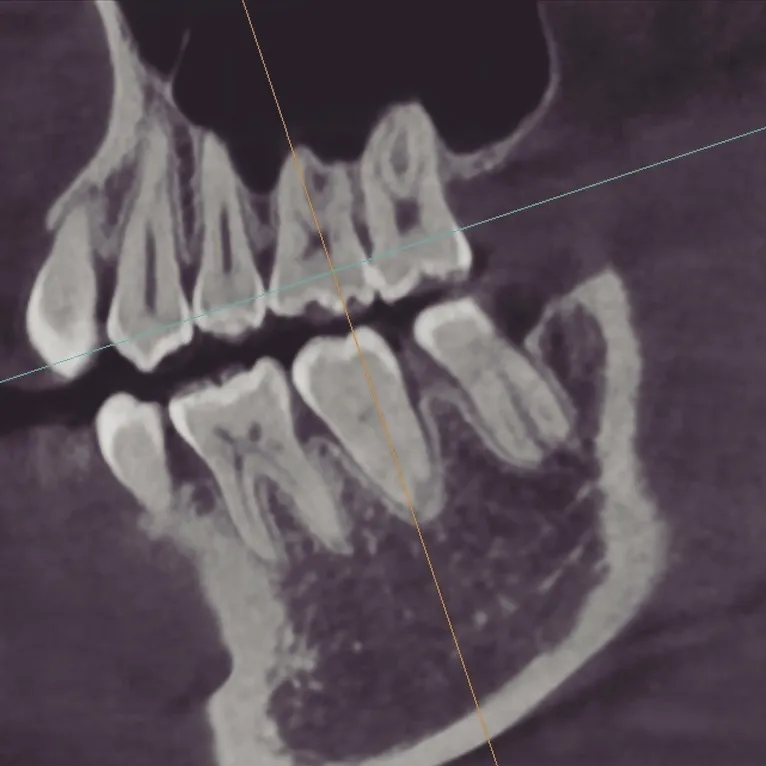

当院ではCBCT(歯科用CT)を導入しており、歯のことを立体的・多角的に把握することができます✨

投稿の写真は院長・私自身のCBCT画像です🙋♂️

こんなにリアルに、立体的に把握できるんです。